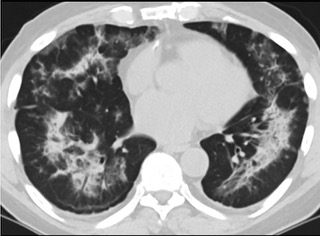

![6AYɨCTfʹ_ܤ]nt]QacT(ïfCT_)](./W020210804330783277896.jpeg)

ݐ6AYɨCTfʹ_ܤ]nt]QacT(ïfCT_)

![6AYɨCTfʹ_ܤ]nt]QacT(ïfCT_)](./W020210804330783485235.jpeg)